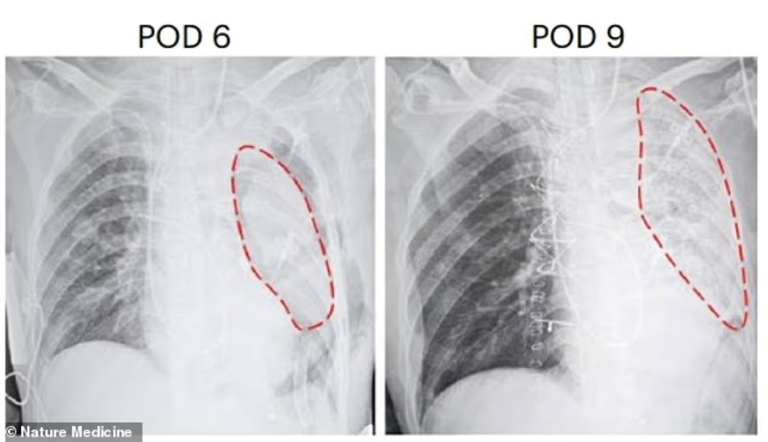

خلال التجربة، لاحظ الفريق أن الرئة بدأت تظهر علامات تلف بعد 24 ساعة وعلامات رفض مناعي جزئي في اليوم الثالث والسادس، ما دفع إلى إنهاء التجربة في اليوم التاسع. ومع ذلك، اعتبر العلماء أن العملية مثلت إثباتًا على إمكانية زراعة الرئة من الخنزير إلى الإنسان وفتحت الطريق أمام مزيد من الابتكارات في مجال زراعة أعضاء من نوع إلى آخر، لمواجهة أزمة نقص الأعضاء على مستوى العالم.